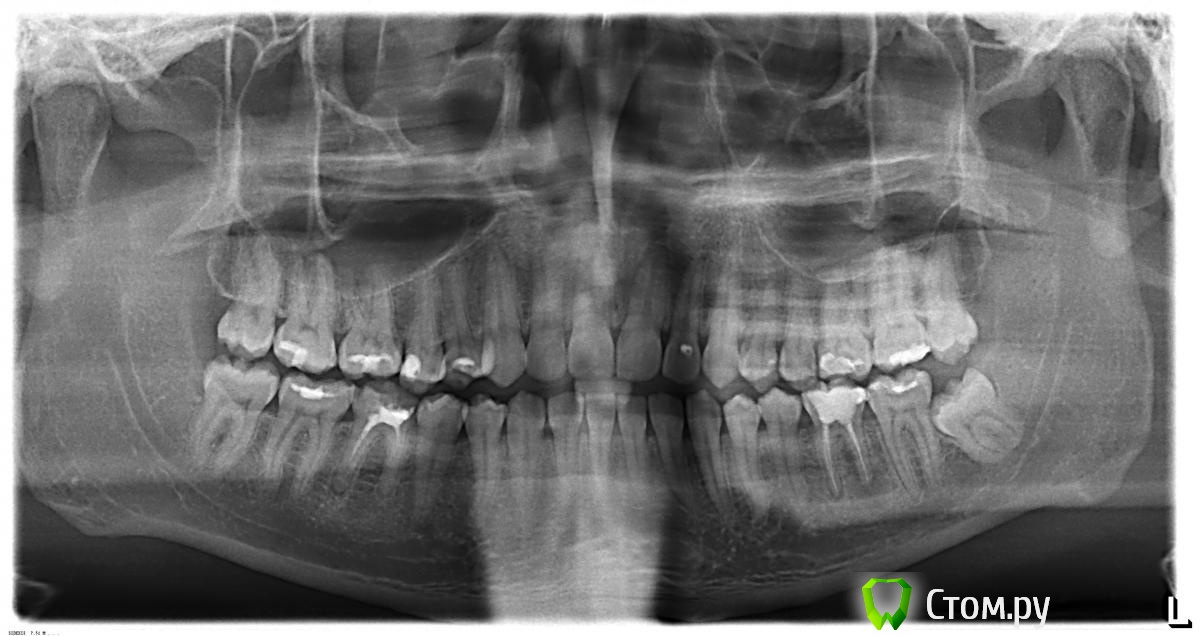

vovka2 Опубликовано 17 января, 2014 Автор Поделиться Опубликовано 17 января, 2014 Спасибо за ответ. Тут случайно нашел ортопантограмму 2-х летней давности, а предыдущие снимки совсем свежие. Есть ли там динамика за 2 года. Ссылка на комментарий

IvanK Опубликовано 17 января, 2014 Поделиться Опубликовано 17 января, 2014 Так удобнее... По этому снимку, рекомендовал бы удалить 38, 28перелечить 36,46 с последующим протезированием. Альтернатива - имплантация Ссылка на комментарий

vovka2 Опубликовано 17 января, 2014 Автор Поделиться Опубликовано 17 января, 2014 Уже за это время все пролечил. Остался вопрос с кистой. Ссылка на комментарий